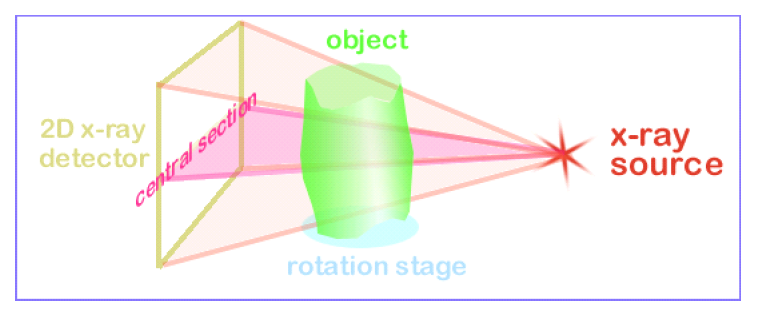

MicroComputed tomography is an X-ray transmission image technique. X-rays are emitted from an X-ray generator, travel through a sample, and are recorded by a detector on the other side to produce radiograph (known as projection image- Figure 1). The sample is then rotated by a fraction of a degree and another projection image is taken at the new position. This procedure is iterated until the sample has rotated 180 or 360 degrees producing a series of projection images.

The projection images are then processed using computer software (typically based on a modified Feldkamp Cone Beam reconstruction algorithm) to show the internal structure of the object nondestructively. This series of images is typically called the reconstructed images or cross sections (figure 2).

The reconstructed images can then be taken and modeled into 3D volumetric objects for quantitative analysis or visualization (Figure 3).

After a projection image is taken, the sample is rotated a fraction of a degree, typical 0.5 degrees or less. (For in vivo scanning, the X-ray source and detector pair are actually rotated. See What is the difference between in vivo and ex vivo scanning). At each step a new projection image is taken. This is done throughout the 360 degree rotation. 180 degrees can be used to shorten the time of the scan as the projection images from 0-180 degrees are the mirror images of the project images from 180-360 degrees. Typically, if you take finer step sizes, the resultant cross-section will be finer as well.